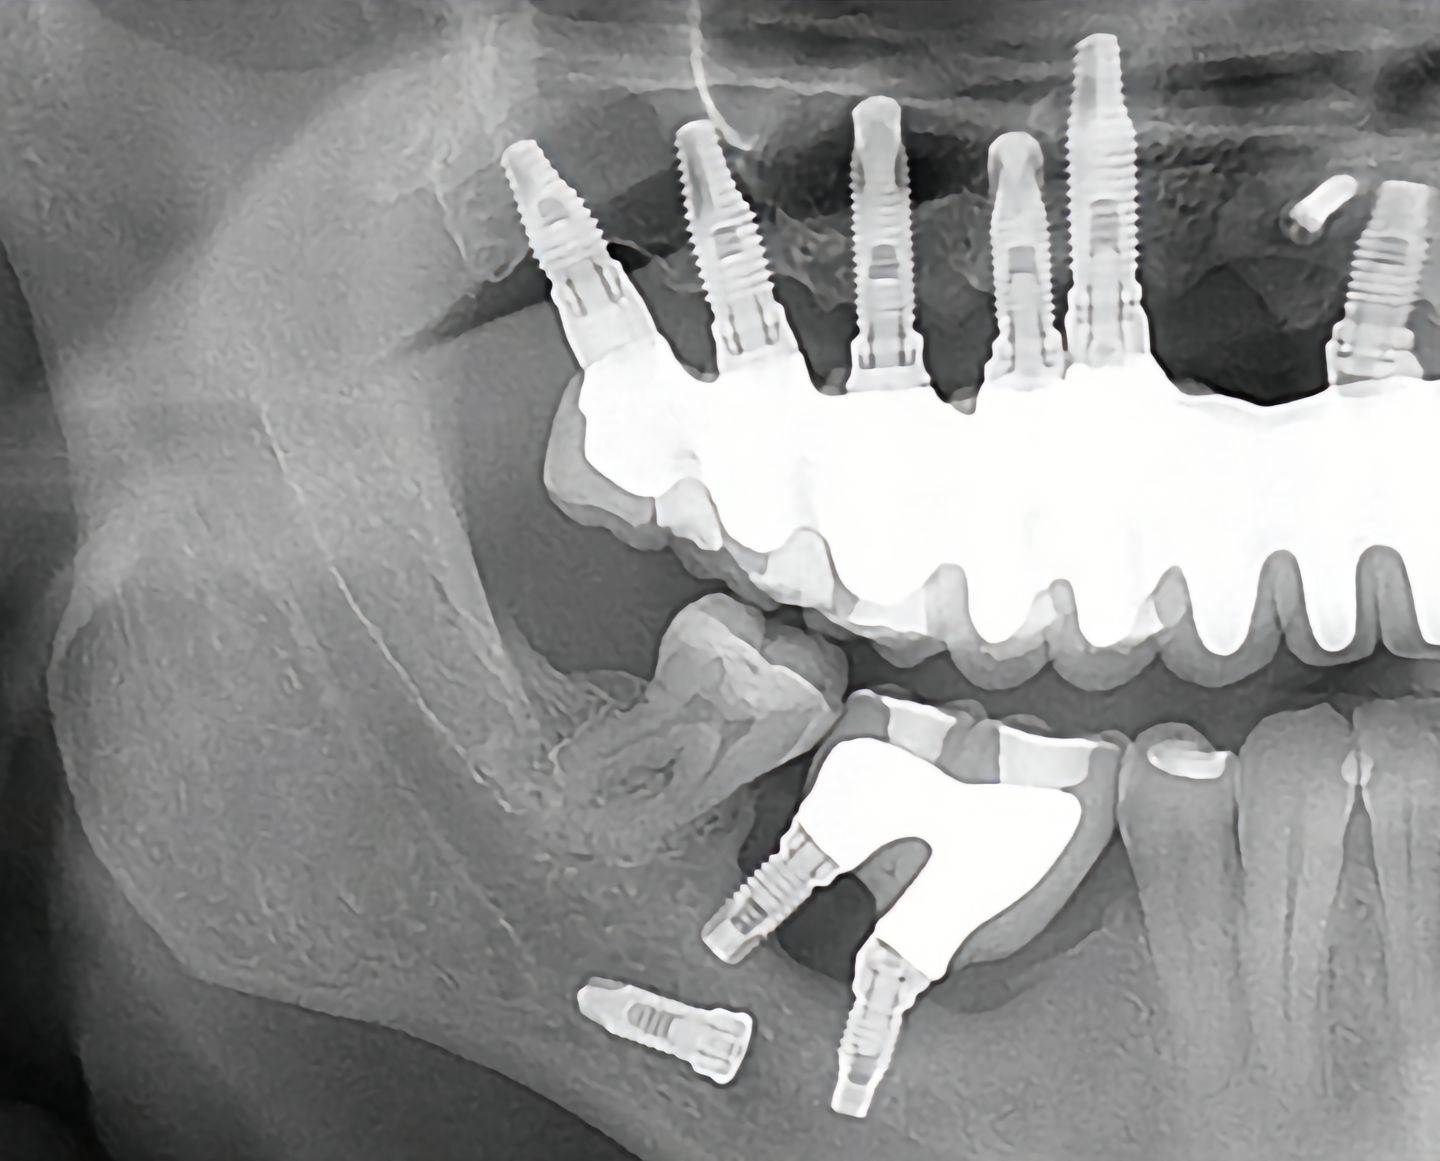

这是什么种植呀

种植体跑哪里了呀